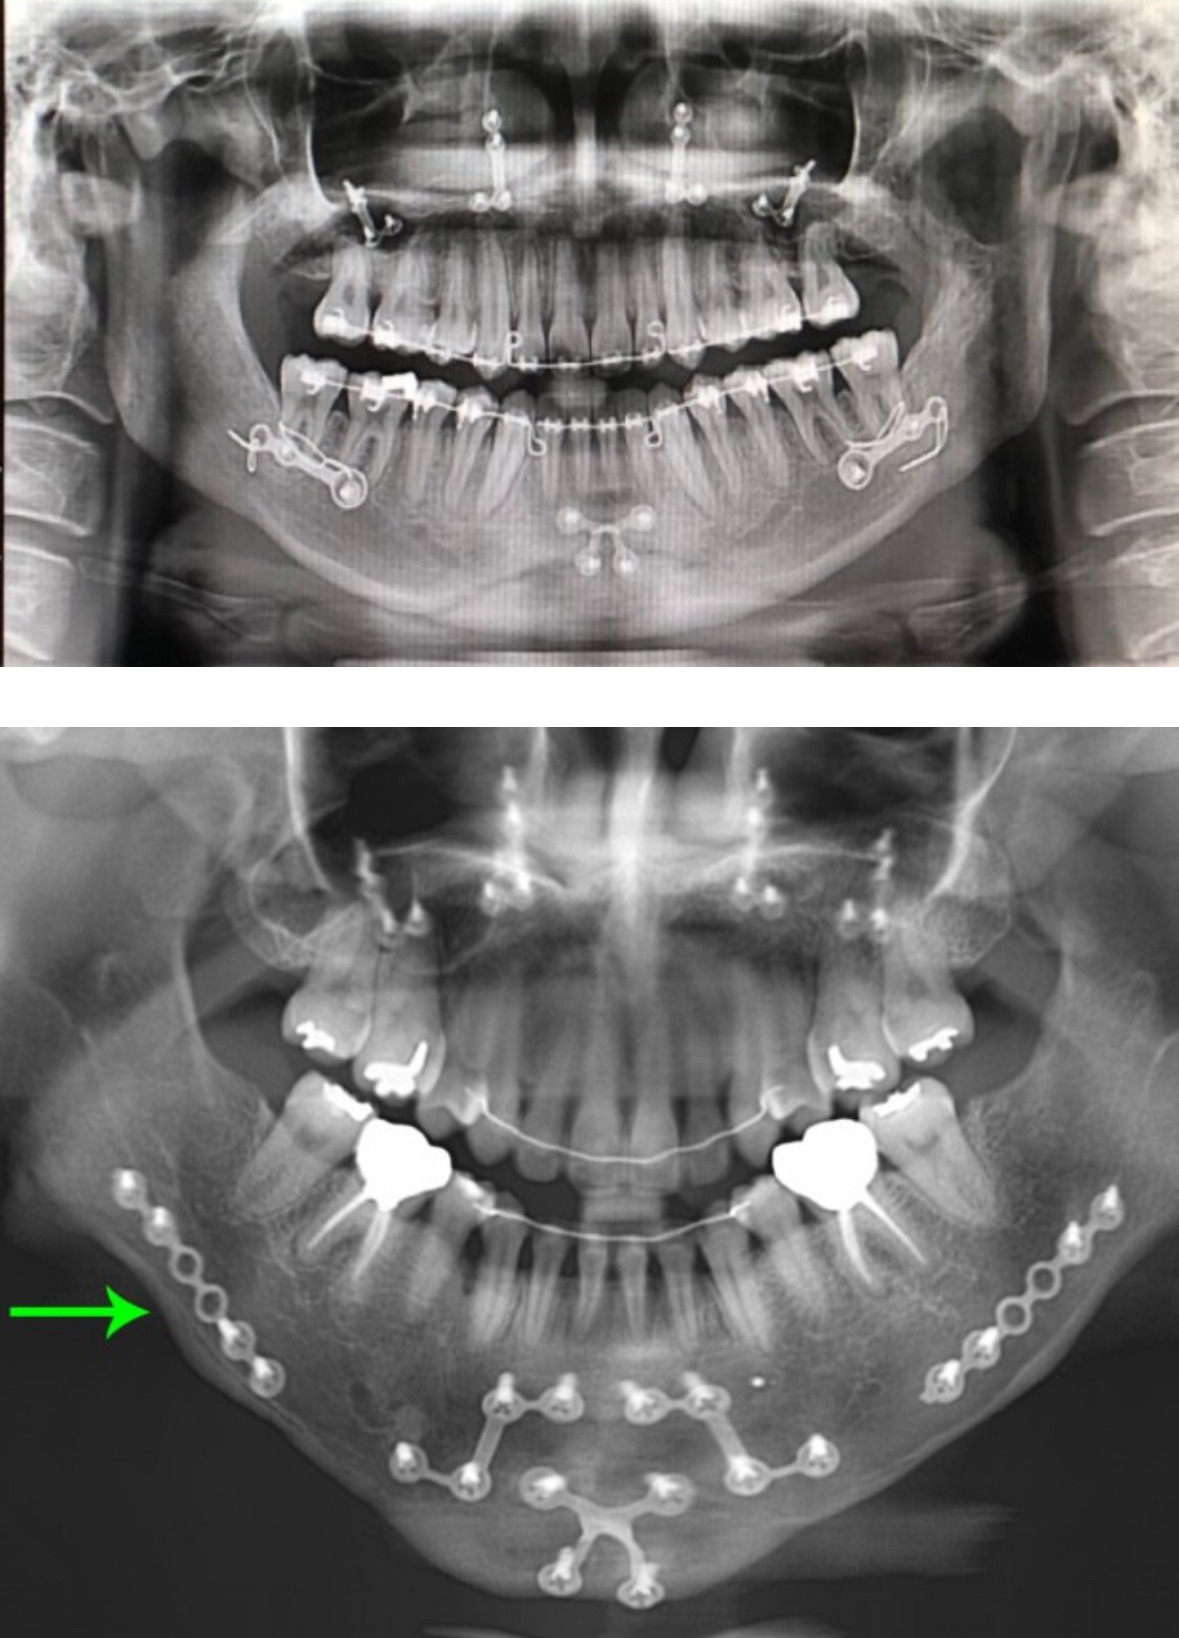

구강악안면 재건술 (악교정술)

흔히 양악수술이라고 부르는데 이건 정식명칭이 아님

많은 사람들이 미용 성형으로 오해하지만

부정교합·턱 변형 교정, 저작 및 발음·호흡 개선 등

치료 목적의 수술임

실제로는 1950년대부터 있었던 아주 오래된 수술이며

치료 목적으로 오랜기간 연구가 진행됨

메인은 구강악안면외과에서 집도하며

치과, 외과와 협업 하는 경우가 대부분임

애초에 성형외과 담당수술이 아니었음

엑스레이 사진 진짜 뭔가 너무 아파보임

치료 목적으로 받았는데 너무 만족함... 수술과정이 미용으로는 절대 안할 수준이긴 해

나도 종합병원 치과에서 받았음. 애초에 주걱턱 심해서. 수술보다 교정이 너무 길고 고통스러웠다